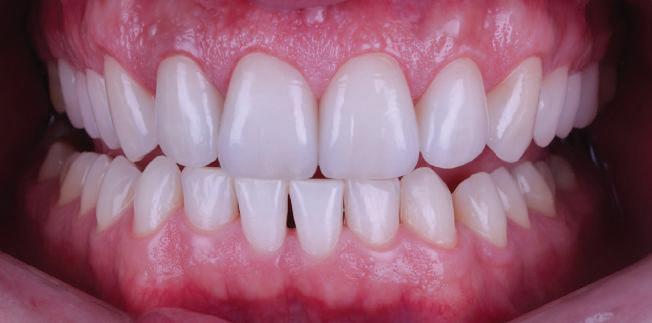

20 Dental Tribune Bulgarian Edition / октомври 2022 г. П ациентите със завършен растеж и скелетни проблеми обикновено представляват предизвикателство за ортодонт ската практика. Необходимостта от изваждане на зъби в комбинация с особеностите на възрастовата ортодонтия изисква особено внима ние. Фокусът върху критично важното значение на позицията на долните резци във връзка с дългосроч ната стабилност и постигането на оптимални оклузални взаимоотношения при затварянето на екстракционните пространства лесно може да излезе извън контрол. Когато към тези чисто кли нични проблеми се добави и стресът от натоваре ната практика, предизвикателството става още по-голямо. Всички тези фактори налагат използ ването на доказан подход с ясни и последовател ни стъпки, в което се разкрива силата на дисциплината „Алекзандър“ – предвидим протокол през целия процес на елиминиране на ротациите, ниве лиране на дъгите, затваряне на екстракционните пространства и финализиране на случая. Именно такъв е и случаят, който презентираме –екстракционен, скелетен клас 3 при възрастен па циент, лекуван по системата „Алекзандър“. ПРЕДВИДИМИ РЕЗУЛТАТИ ПРИ ПАЦИЕНТИ СЪС ЗАВЪРШЕН РАСТЕЖ И СКЕЛЕТЕН КЛАС 3, ИЗПОЛЗВАЙКИ ЕКСТРАКЦИОННО ЛЕЧЕНИЕ ПО ДИСЦИПЛИНАТА „АЛЕКЗАНДЪР“ Д-р Радой Димитров, България Преди започване на лечение клиничен случай | ортодонтия Фиг. 1а–1e Преди започване на лечение. Пациентът пристига в практиката с основното оплакване от невъзмож ност за нормално дъвчене. Снета е цялата необходима диагностична ин формация. Фиг. 1f–1h Снимки в профил и анфас. Фиг. 1i–1k Панорамна снимка, телерентгенография и анализ на телерент генография. Фиг. 1а Фиг. 1d Фиг. 1f Фиг. 1g Фиг. 1h Фиг. 1e Фиг. 1b Фиг. 1c Фиг. 1i Фиг. 1j Фиг. 1k

21Dental Tribune Bulgarian Edition / октомври 2022 г. ДИАГНОСТИЧНИ РЕЗУЛТАТИ: 1. Възраст на пациента: 21 години 2. Скелетен клас III (ANB 0) 3. Зъбен клас 3 4. Ръбцова захапка във фронта, кръстосана в дисталните участъци 5. Тясна горна челюст 6. Overjet – 0 мм, Overbite – 0 мм 7. Несъответствие на горната с долната средна линия 8. Единични контакти в ЦО 9. Хиподивергентен тип на растеж SN/MP – 33.5 10. Неравен гингивален контур 11. Неравна линия на усмивката 12. Тенденция за рецесии в долен фронт ПРЕПОРЪЧИТЕЛНО ЛЕЧЕНИЕ: Пълно ортодонтско лечение с метални брекети „Алекзандър“ Корекция на клас 3 захапката в областта на кучешките зъби с екстракция на първите пре молари в долна челюст Корекция на кръстосаната захапка в дистални участъци Коригиране на ръбцовата захапка във фронта Подобряване на ОJ и OB на пациента Стрипинг в долен фронт Подреждане на зъбите в горната и долната челюст Професионално хигиенизиране и профилактични дентални прегледи са препоръчителни на всеки 6 месеца. 1-ви месец След 1 месец са залепени брекети в горната челюст – поставена е еластична дъга. 016 NiTi. В долната челюст са елиминирани ротациите, поставена е стоманена дъга. 016SS, закалена с ток, и еластична верижка за затваряне на пространствата. 3-ти месец В долната челюст е поставена трета дъга – 17 x 25 NiTi с къси лигатури и верижка

В горната челюст се затварят пространствата с дъга .016SS и верижка. 5-и месец На 5-ия месец след залепяне на брекетите в долната челюст е поставена стоманена дъга 16 x 22 SS с четвъртито сечение, омега луп и тай бек. В горната челюст е поставена дъга 17 x 25 NiTi. Поради липсата на стабилни оклузални контакти са поставени лингвални верижки в областта на моларите, за да се предотврати нежелана ротация на 7-ите зъби. 6-и месец На 6-ия месец от началото на лечението са екстрахирани долните първи премолари, поставена е дъга 16 x 22 SS със затваряща чупка teardrop. Чупката се активира всеки месец по 1 мм с чинч-бек. клиничен случай | ортодонтия СТЪПКИ НА ЛЕЧЕНИЕТО Начало на лечението Лечението започва с поставяне на апарат за бърза експанзия в горната челюст. През първия месец от лечението са направени 24 оборота на апарата за експанзия. Залепени са брекети в долната челюст, поставена е дъга 17x25 CuNiTi, като са предпи сани клас 3 ластици (1/4”,4 1/2 oz) по време на сън, за да се осигури контрол върху торка на долните резци. Фиг. 2а Фиг. 3a Фиг. 4a Фиг. 3b Фиг. 4b Фиг. 3c Фиг. 4c Фиг. 3d Фиг. 4d Фиг. 3e Фиг. 4e Фиг. 5a Фиг. 5b Фиг. 5c Фиг. 5d Фиг. 5e Фиг. 6a Фиг. 6b Фиг. 6c Фиг. 6d Фиг. 6e Фиг. 7a Фиг. 7b Фиг. 7c Фиг. 7d Фиг. 7e Фиг. 2b Фиг. 2c Фиг. 2d

Dental Tribune Bulgarian Edition / октомври 2022 г.22 клиничен случай | ортодонтия 14-и месец В горната и долната челюст са поставени последни стоманени дъга с омега луп и тай бек – 17 x 25 SS с четвъртито сечение. Назначени е ластик за средната линия в комбинация с клас 3 ластик (1/4”, 6 1/2 oz). Контролни рентгенографии 13-и месец Екстракционните пространства са затворени. Направена е контролна панорамна снимка за оценка позицията на корените. Взето е решение за презалепване на брекетите на 12, 22 и пръстените на 36 и 46. 21-ви месец Средната линия в горната и долната челюст съвпадат. Ластиците са спрени. Свалени са пръстените и брекетите в горната и долната челюст, зигзаг ластици не са използвани поради благоприятните оклузални взаимоотношения. Фиг. 11j Ортопантомография в края на лечението. Фиг. 11k Телерентгенография след края на лечението. Фиг. 11l Анализ на телерентгенографията след лечението. Фиг. 11m Последователност на дъгите в горната и долната челюст Фиг. 11n Суперимпозиция на PreOp и PostOp ортопантомографии. 10-и месец Затварянето на пространствата е предвидимо и контролирано, без да се отварят пространства в зъбната дъга. Фиг. 8a Фиг. 8b Фиг. 8c Фиг. 8d Фиг. 8e Фиг. 10a Фиг. 10b Фиг. 10c Фиг. 10d Фиг. 10e Фиг. 9a Фиг. 9b Фиг. 9c Фиг. 9d Фиг. 9e Фиг. 9f Фиг. 11a Фиг. 11f Фиг. 11j Фиг. 11l Фиг. 11m Фиг. 11n Фиг. 11k Фиг. 11g Фиг. 11h Фиг. 11i Фиг. 11b Фиг. 11c Фиг. 11d Фиг. 11e

Dental Tribune Bulgarian Edition / октомври 2022 г. 23клиничен случай | ортодонтия реклама Лечението е продължило 21 месеца. Проведено е домашно избелване с индивидуални шини. За автора: Д-р Радой Димитров завършва с отличие Факултета по дентална медицина към МУ–София през 2015 г. В продължение на 5 години работи в няколко водещи практики в София, като през 2019 г. заедно със своята съпру га д-р Траяна Димитрова основават собствена практика в гр. Гоце Делчев –Dimitrovi Dental Care. Посещава редица курсове за повишаване на квалификаци ята, но най-сериозен тласък в развитието на ортодонтската си практика получава след завършването на комплексната ортодонтска програма, воде на от д-р Иван Горялов, базирана на дисциплината „Алекзандър“ – система с повече от 50 години опит в целия свят. Д-р Димитров е член на Българския изследователски клуб „Алекзандър“. Взе ма участие като гост-лектор в симпозиума с международно участие The Power of the Alexander Discipline, който се проведе на 14–15.05.2022 г. С д-р Ди митров можете да свържете на тел. +359885 252 025. Заключение Представеният случай е ярък пример за възможностите и красо тата на дисциплината „Алекзандър“ – приложен е утвърден под ход с ясни правила и са постигнати очакваните цели. Резулта тът ще бъде дългосрочно стабилен, тъй като са спазени всички правила, които се отнасят към максимално комфортната пози ция на зъбите в края на лечението. Постигнати са красива усмив ка и стабилна оклузия. ПОСТИГНАТИ РЕЗУЛТАТИ ОТ ЛЕЧЕНИЕТО 1. Коригирана ръбцова захапка 2. Коригирана клас 3 захапка в областта на ку чешките зъби 3. Коригирана кръстосана захапка в дисталните участъци 4. Коригиран овърджет и овърбайт 5. Разширена е горната зъбна дъга 6. Подредени зъби в горната и долната челюст 7. Постигната е стабилна захапка с множество контакти в ЦО 8. Драматично е подобрена дъвкателната функ ция 9. Подобрена е линията на усмивката ДРУГИ ПРОВЕДЕНИ ДЕНТАЛНИ ПРОЦЕДУРИ 1. Домашно избелване на зъбите 2. Екстракция на мъдреците Фиг. 12a Фиг. 12b Фиг. 12c Фиг. 12eФиг. 12d Фиг. 12f Фиг. 12g Информация за дати, цени и отстъпки www.bracescourses.com 0889 22 55 01 Практически курсове лектор д-р Иван Горялов Дисциплината „Алекзандър“ ПЪТЯТ КЪМ СУПЕРУСМИВКИТЕ 100% връщане на цялата сума, ако не сте удовлетворени след преминаване на Ниво 1 Директно и индиректно залепяне на брекети Анализ, диагноза и план на лечение Лечение на клас 2 дълбока захапка Екстракционно лечение Лечение на клас 3 отворена захапка НИВО 5НИВО 1 НИВО 2 НИВО 3 НИВО 4